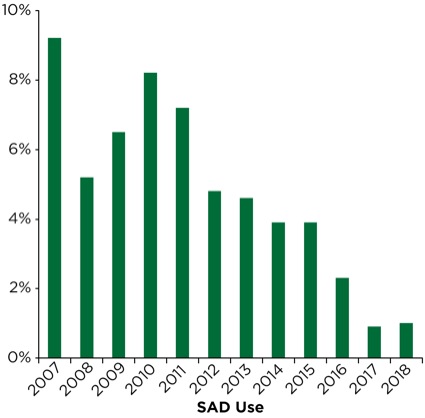

Utilization of the SAD in its role as a rescue ventilation and intubation conduit appears to be undergoing major changes (Table 10). As presented earlier in Figure 1, the use of the SAD peaked following widespread distribution and ready access at the beside for NORA emergency intubations as well as in the OR. In our institution’s “post-ASA guideline ready” period from 1996 to 2006, the SAD was deployed, in some role, in nearly one in six NORA emergency airway interventions. VL was introduced in the mid- to late 2006 and fully deployed to NORA locations in early 2007. There was a precipitous drop in the rescue use of the SAD in 2007, to about 9% following VL deployment. In the following five-year period, its use plateaued in the 4% range.

Over the past three-year period (2016-2018), our department has deployed an improved disposable DL model (BritePro, Flexicare) that may have an impact on patient care. Utilization of a video laryngoscope as a primary device or in a rescue role has changed little over three years and accounts for 50% to 60% of airway interventions. Likewise, wide distribution of disposable FFBs, in a variety of sizes, has led to a slight uptick in the role FFB plays in NORA airway management. However, the rescue role of the SAD has fallen to approximately 1% over the last two years (Figure 7).